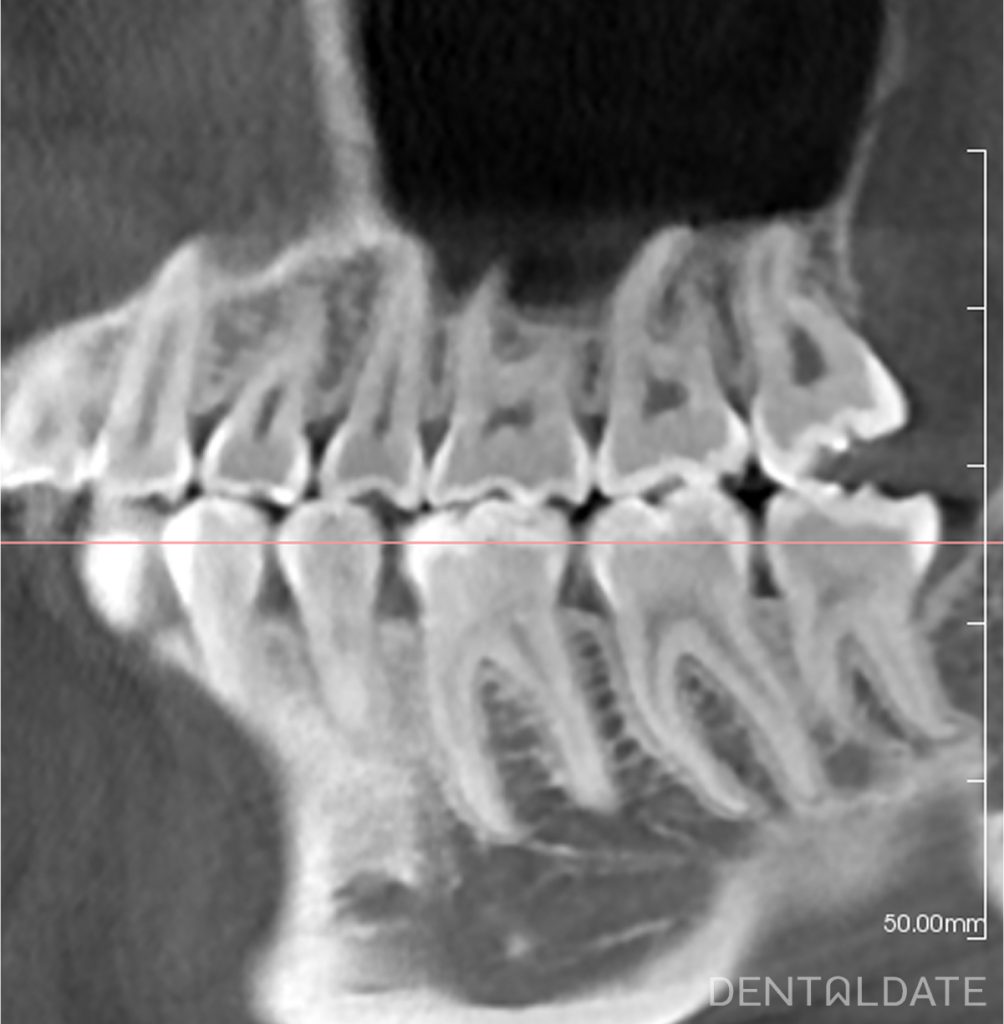

This case exemplifies a situation where the roots of an upper wisdom tooth extended into the maxillary sinus.

The extraction was challenging; a root fragment fractured during the procedure, but was successfully retrieved.